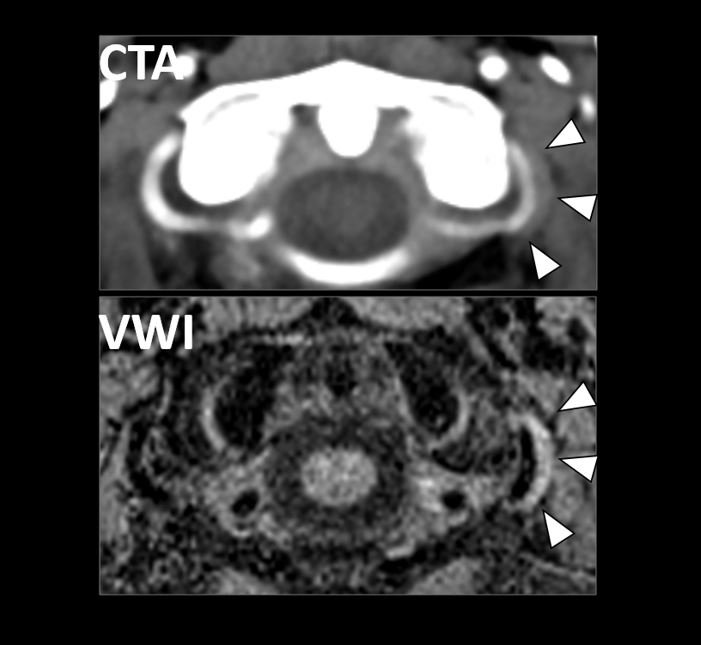

Vessel Wall Imaging of a Carotid Web (May 2022)

We report imaging findings on CTA and VWI of a carotid web that was the most likely cause of ischemic stroke.